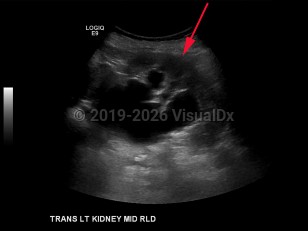

Hydronephrosis

Polycystic kidney diseasePolycystic kidney disease